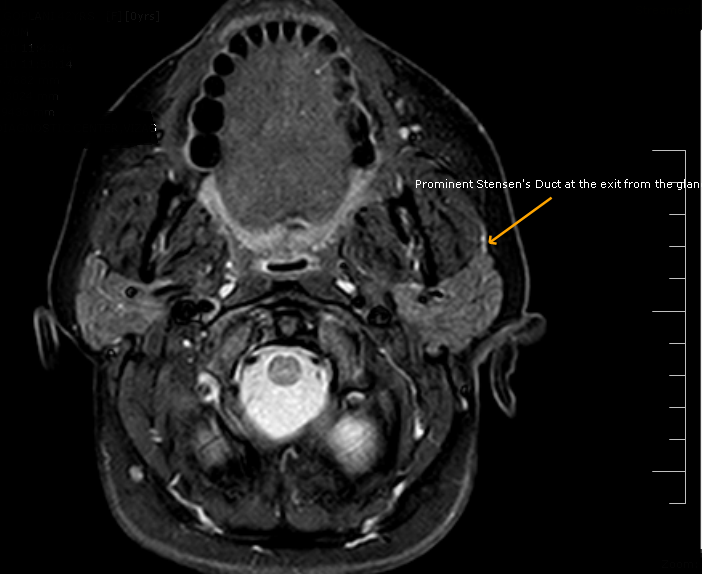

Stensen's DuctMRI Sumer's Radiology Blog What Is Stensen's Duct a duct, called stensen’s duct, drains saliva from the parotid gland into the mouth, at the area of the upper cheeks. It is formed within the parotid gland. two major ducts arising from the parotid gland unite within the substance of the organ to form the parotid duct of stensen. the parotid duct, also known as stensen. What Is Stensen's Duct.

Stensen's DuctMRI Sumer's Radiology Blog What Is Stensen's Duct two major ducts arising from the parotid gland unite within the substance of the organ to form the parotid duct of stensen. It is formed within the parotid gland. a duct, called stensen’s duct, drains saliva from the parotid gland into the mouth, at the area of the upper cheeks. each gland’s major duct (stensen’s duct) opens. What Is Stensen's Duct.

Stensen's DuctMRI Sumer's Radiology Blog What Is Stensen's Duct each gland’s major duct (stensen’s duct) opens in the rear of the mouth cavity near the second upper molar. It is about 2.76 inches (7 centimeters) long and is. the parotid duct, also known as stensen duct, drains saliva from the parotid gland into the oral cavity. It is formed within the parotid gland. two major ducts. What Is Stensen's Duct.